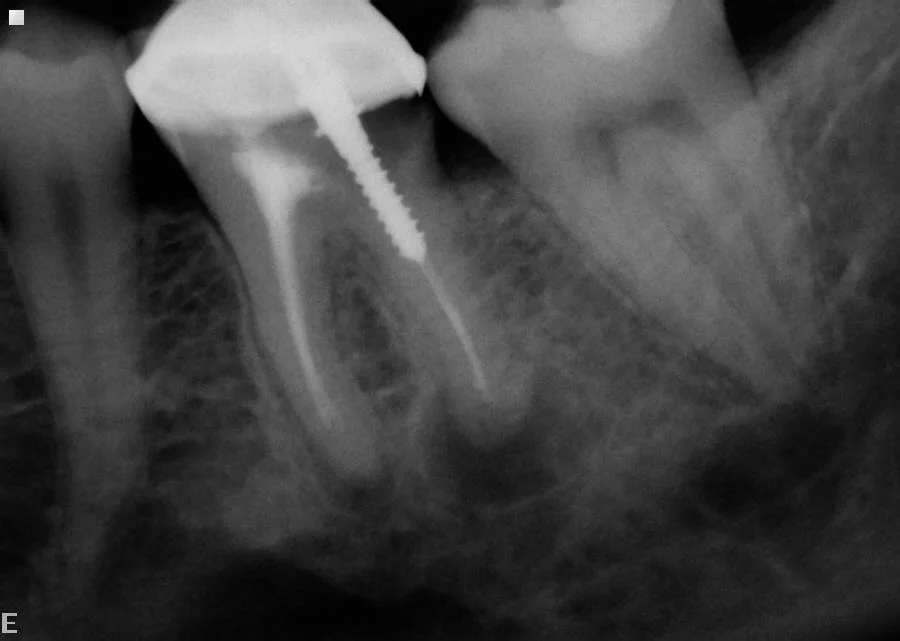

Both roots are infected and the crown is held in place with a metal screw. In addition there is decay under the crown. The options are to remove the crown and screw, re-do the root treatment, rebuild the tooth and make a new crown OR extract the tooth.

Crown and post were removed and we successfully root treated three roots and rebuilt the tooth in preparation for a new crown.